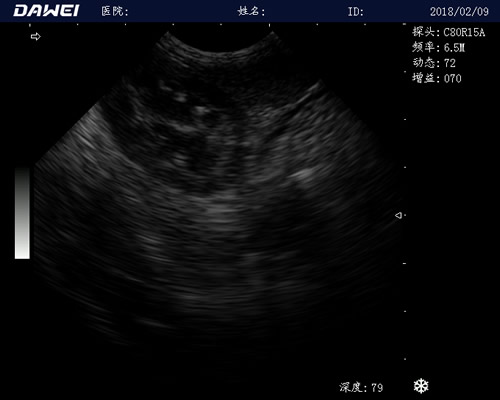

MT15推车式兽用B超仪

全数字动物超声诊断仪

·探头频率:支持≥5种变频,临床效果更好体现

·中小动物的肝、胆,脾、肾、膀胱、子宫、妊娠等各组织器官的检查和病变的诊断